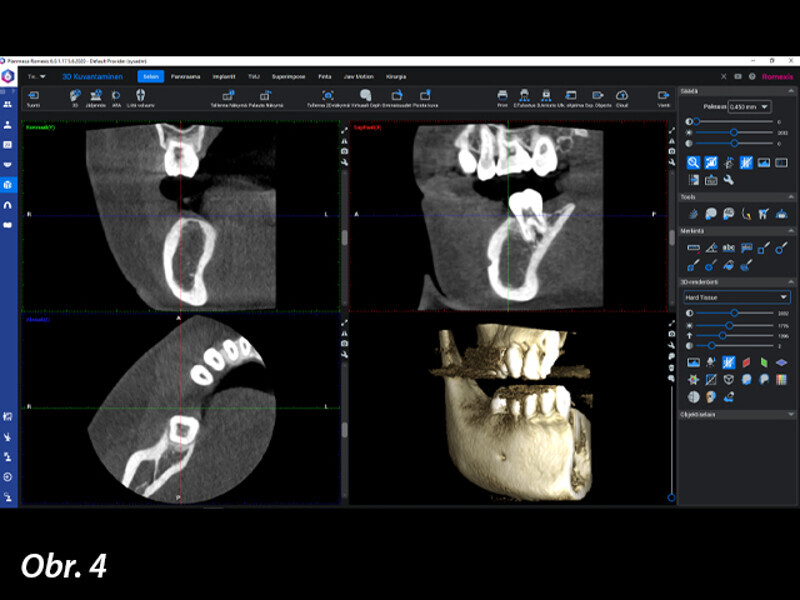

Řízená implantologie za použití řešení Planmeca all-in-one